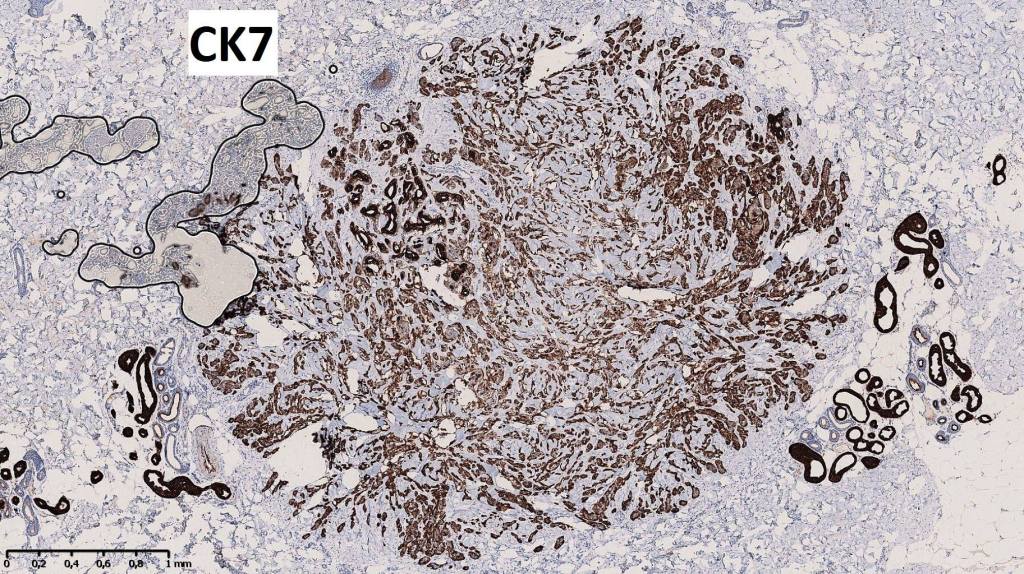

•Epithelial cells are EMA, CEA & GCDFP-15 +ve, myoepithelial cells are S100, SOX10, SMA & MSA +ve

•Well circumscribed unencapsulated, nodular/multinodular silhouette composed of an admixture of epithelial & mesenchymal elements